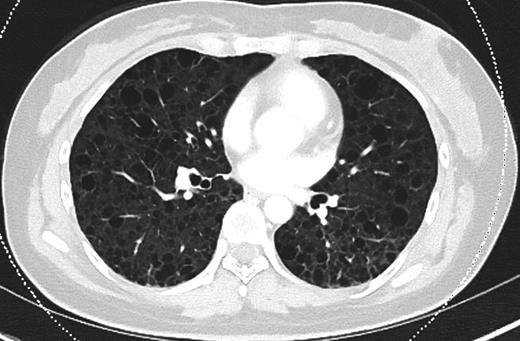

Upon admission, the patient's chest x-ray (CXR) was notable for bilateral interstitial infiltrates, and she was therefore started on empiric broad-spectrum antibiotics and oseltamivir. She was ventilated with lung-protective settings and paralyzed to alleviate ventilator dyssynchrony. Bronchoscopy revealed DAH and bronchioalveolar lavage cultures yielded Influenza A infection. She was started on high-dose methylprednisolone for her DAH, and inhaled nitric oxide (iNO) was added to optimize oxygenation. After a transient period of improvement, new infiltrates were appreciated on CXR, prompting computed tomography (CT) of her chest. This revealed multiple cysts throughout the lung parenchyma, suspicious for the diagnosis of LAM (Fig. 1).

CT chest (axial slices in lung window) demonstrating innumerable cysts scattered throughout all lung fields without basal/apical predilection or cardiophrenic sparing.